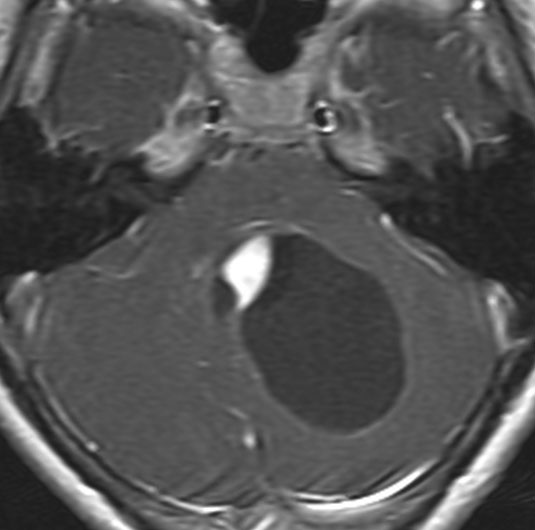

成人では,増大しないmassとして腫瘍が発見されます。T2強調画像でわずかな高信号,ガドリニウムでほとんど増強されない,無治療で経過観察しても全く変化がないということがしばしばであるので,視野欠損などの症状があっても,このようなものを疑えば生検手術もせずに経過のみをみたほうがいいです。